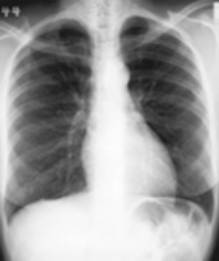

Dit is het meest uitgevoerde onderzoek op de dienst radiologie. Een thoraxfoto kan om veel redenen worden aangevraagd.

Als routine onderzoek bij een screening vb.

Bij vermoeden van een longletsel |

Bij kortademigheid |

Als opvolging van het effect van een behandeling |

Bij een trauma van de borstkas |

Er zijn in princiepe twee manieren om een thorax opname te maken:

De

staande opname waar meestal een face en een profiel opname wordt

genomen |

liggende opname bij een patiënt die niet kan staan, normaal enkel

face opname tenzij anders aangevraagd |